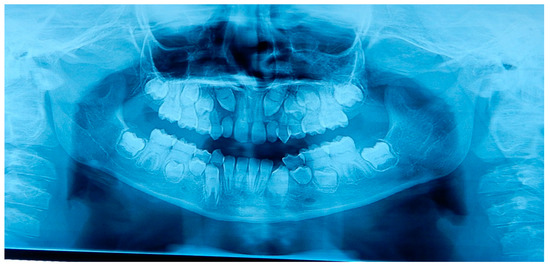

2.2. Patient B